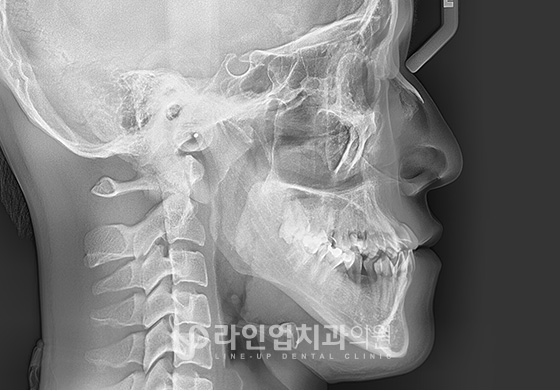

Before and After

After